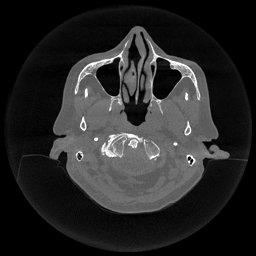

The results for simulated noisy data are shown in Fig. 2. The first and third rows display two representative slices from the test set, and the second and fourth rows present the corresponding error maps. The traditional WCE method suppresses cupping artifacts and recovers some missing anatomical structures but still shows noticeable deviations from the ground truth. Predictions from the four diffusion-based models demonstrate a markedly improved ability to restore anatomical structures. Among them, cDDPM fails to fully reconstruct the patient bed and retains residual noise in its outputs. This noise is attributable to an incomplete reverse denoising process rather than residual Poisson noise, as evidenced in our noise-free experiments (Fig. 5 in the Appendix). PatchDiffusion, diffusionGAN, and I2SB achieve similar visual quality, with I2SB producing the cleanest and most consistent reconstructions.

The experimental results on clinical head data are shown in Fig. 4. The reference images were reconstructed using the fast iterative shrinkage-thresholding algorithm (FISTA) with total variation regularization from non-truncated projection data. In the WCE reconstructions (Fig. 4(b)), severe truncation prevents accurate recovery of anatomical structures outside the FOV. Despite being trained solely on simulated data with a domain gap, all deep learning models can restore a substantial portion of the missing anatomy. Among them, the diffusion-based methods recover soft-tissue boundaries more faithfully than the conventional deep learning approach FBPConvNet, highlighting their stronger image generation capability. However, cDDPM reconstructions exhibit more noticeable noise than those from other methods, consistent with the simulated data results. The patchDiffusion model introduces artifacts within the FOV, likely due to its patch-wise processing strategy. While I2SB shares the same limitations as other diffusion models in perfectly restoring soft-tissue detail, it produces fewer residual noise patterns and fewer artifacts within the FOV boundaries. Overall, Fig. 4 demonstrates the strong efficacy of I2SB in reconstructing real CBCT data.